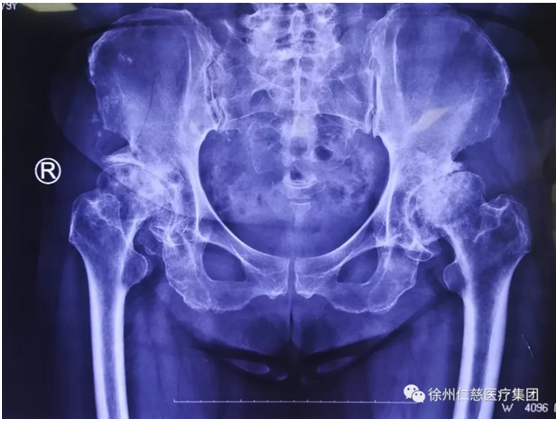

郝醫(yī)生一聽(tīng)他這么能喝酒,點(diǎn)點(diǎn)頭,安排他攝片,果然,顯示右側(cè)股骨頭壞死,需要做全髖關(guān)節(jié)置換。

(術(shù)前)